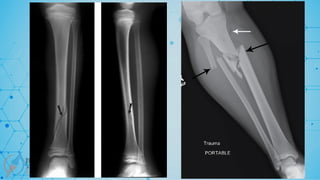

Diaphyseal segment 2

Q. Is the fracture simple or multifragmentary?

A – Simple fracture (with a single circumferential fracture)

B – wedge (with one or more intermediate fragments)

C – Multifragmentary(multiple fragments, noncontact btwn P & D)

AO / OTA Classification

Group;

Spiral or twisting forces will produce a

Simple spiral (X2-A1), spiral wedge (X2-B1), or spiral fragmented complex

# (X2-C1)

Bending forces produce a

Simple oblique ((X2-A2), simple transverse (X2-A3), or Bending wedge (X2-

B2), fragmented wedge (X2-B3), complex # (X2-C3)

C2 fractures in the grouping is segmental by definition